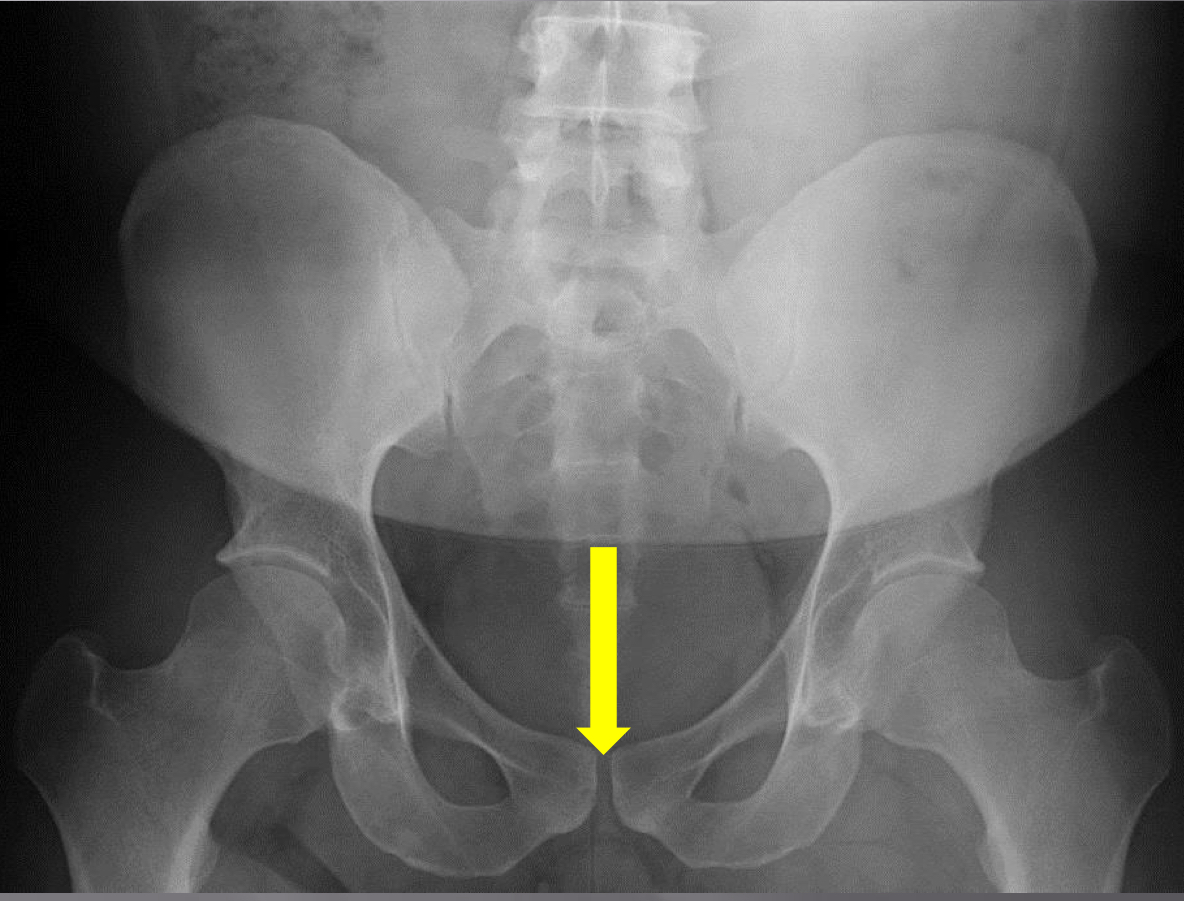

What view is this?

AP (Anterior to Posterior) LumboPelvic

What is this?

Femur Heads

What is this?

Superior Iliac Crests

What is this?

Lateral Iliac Crests

What is this?

Ischial Tuberosites

What is this?

Obturator Foramen

What is this?

S2 Tubercle

What is this?

Pubic Symphysis

What is this?

Sacral Groove

What is this?

Lateral aspect of sacrum

What is this?

Medial Aspect of Ilium